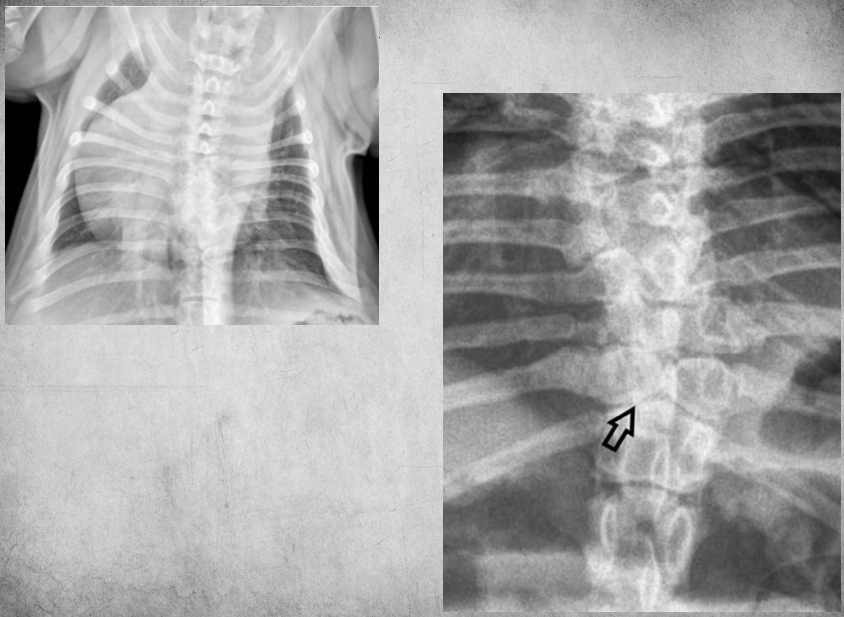

identify pathology

Nutritional Hyperparathyroidism Decreased contrast between bone and soft tissue. Pathological fractures/ pseudofractures. Bendy bones. Painful